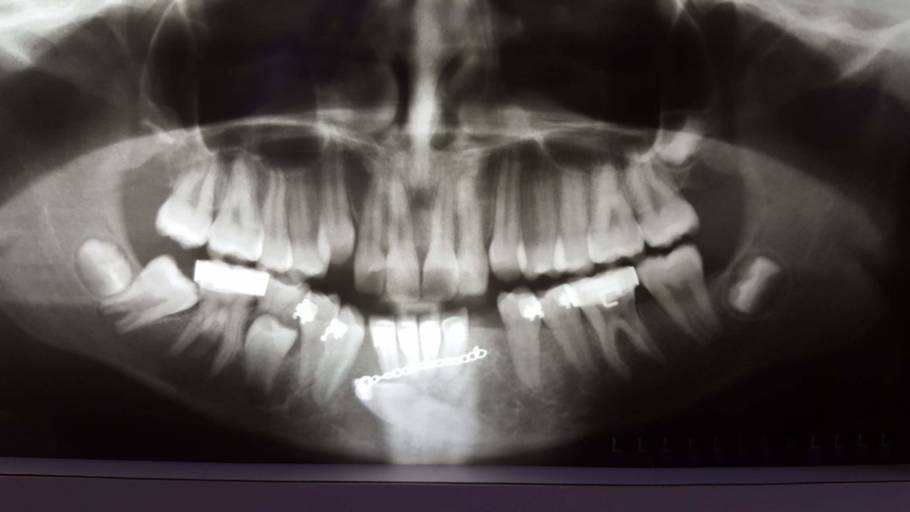

Does it look like I may need braces?

Hi, I have an upcoming orthodontist appointment next month because my mom is worried about my teeth. I’m nervous to know if I’ll need braces or not and I want an idea of what the Ortho would say. What do you think?

You are a great candidate for orthodontic treatment. It appears that your maxillary (upper) teeth are slightly flared, bringing these teeth back into proper alignment will close the space between your maxillary and mandibular front teeth. In the bottom right picture, it is hard to see if your posterior (back) teeth are touching. If they are, then you are considered to have an "open" bite. Your upper front teeth should slightly overlap your lower front teeth allowing you to bite into and tear your foods easily. More than likely, the orthodontist will recommend a full orthodontic treatment case placing you in treatment for 12-18 months, followed by retention.